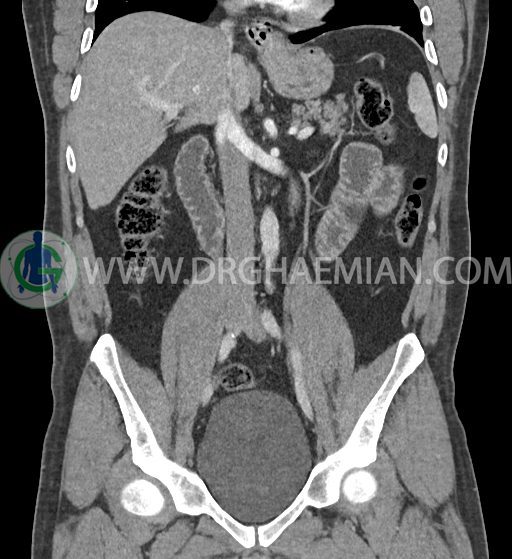

سی تی اسکن شکم و لگن با استفاده از اشعات ایکس تصاویر عرضی از ناحیه شکم و لگن ایجاد میکند. در این کیس فتق هیاتوس و هیدرویورترونفروز دیده می شود.

در سی تی اسکن اسپیرال شکم و لگن با کنتراست خوراکی و وریدی (مولتی دیدکتور 16 با مقاطع ظریف و بازسازی های ساژیتال و کرونال) :

-sliding hiatal hernia به ابعاد 60x44mm با جابجایی JE.junction و فوندوس معده به فضای مدیاستن خلفی دیده می شود.

-هیدرویورترونفروز جزئی دو طرفه دیده می شود که می تواند ثانویه به اتساع مثانه باشد.